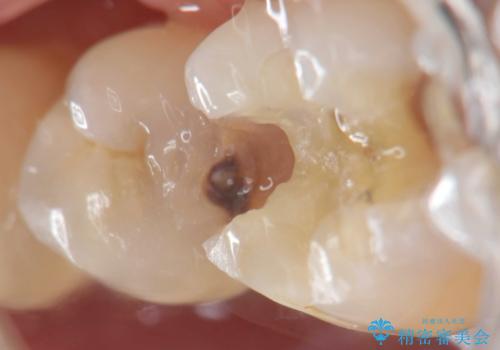

保険適応の白い詰め物レジンインレー下に再発した大きな虫歯治療

- 以前治療した歯の違和感、しみる感じの改善を求めて来院されました。

保険適応の素材、レジン素材による修復が行われていますが、X線写真より修復物の下には透過像(黒い影)が認められ、症状からも虫歯の再発が強く疑われます。